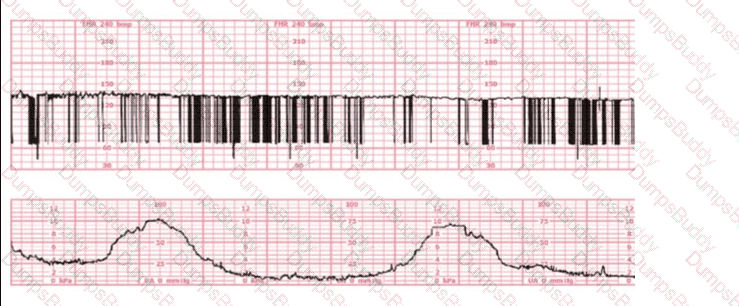

A woman at 38-weeks gestation is admitted to labor and delivery following a fall down the stairs three hours ago. She started feeling contractions in the ambulance. The fetal heart rate tracing shown is on initial evaluation and represents 25 minutes. This tracing is most consistent with a